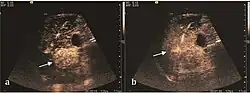

On CEUS examination, early HCC has an iso- or hypervascular appearance during the arterial phase followed by wash out during portal venous and late phase. There are studies showing that the wash out process is directly correlated with the size and features of neoplastic circulatory bed. Thus, highly differentiated HCC illustrates the phenomenon of late or even very late "wash out" while poorly differentiated HCC has an accelerated wash out at the end of arterial phase. It is therefore mandatory to analyze all these three phases of CEUS examination for a proper characterization of liver nodules. Tumor wash out at the end of the arterial phase allows the HCC diagnosis with a predictability of 89.5%. Some authors consider that early pronounced contrast enhancement of a nodule within 1–2 cm developed on a cirrhotic liver is sufficient for HCC diagnosis. These results prove that for a correct characterization of the lesions it is necessary to extend the examination time to 5 minutes or even longer.

B-mode ultrasonography is unable to distinguish between regenerative nodules and borderline lesions such as dysplastic nodules and even early HCC. Doppler examination also has a low sensitivity in differentiating dysplastic nodules from early HCC. Doppler signal may be absent in both regenerative and dysplastic nodules. Some authors indicate the presence of venous type Doppler flow which reflects the portal venous nutrition of the nodule as a characteristic feature of dysplastic nodules and early HCC (Minami & Kudo, 2010). Other authors noticed the presence of an arterial flow with small frequency variations and a normal resistivity index. On CEUS examination both RN and DN may have quite a variable enhancement pattern. Generally, both nodules enhances identically with the surrounding liver parenchyma after UCAs injection. Dysplastic nodules are hypovascular in the arterial phase. In case of highgrade dysplastic nodule sometimes a hypervascularization can be detected, but without associating "wash out" during portal and late CEUS phases. In these cases, biopsy may clarify the diagnosis.